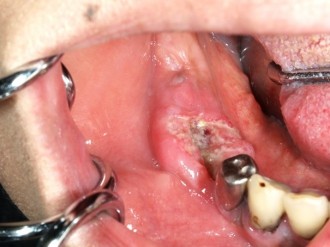

癌の発生する部位や病期(癌の進行度)によって様々です。癌表面の特徴としては、ぶつぶつしていたり、赤や白色に変色している、かたい腫瘤(こぶのような盛り上がり)や潰瘍(えぐれたような形態)を形成していることがあり、時に簡単に出血したり痛みが出ることもあります。病気が進むにつれて噛みにくさや飲み込みにくさ、発音のしにくさが出てきたり、頸部(くび)のリンパ節への転移、遠隔転移(肺、骨、肝臓等)を生じるようになります。

舌癌

頬粘膜癌

上顎歯肉癌

下顎歯肉癌